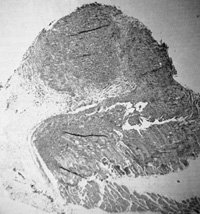

Fig,5. B-Cell lymphoma of nude mouse induced by

injection of mouse with cells induced to grow by GaLVH Cells are

human as determined by karyotype analysis. (From P Markham, F Ruscetti.

Z. Salahuddin, R Gallagher. and R. Gallo. in press)